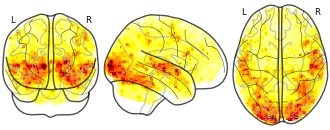

"name": "Multi_VBMsmaller_fMRIenhanced",

"description": "Multi-modal analysis in BPD. Brain regions exhibiting smaller gray matter and enhanced activation during emotion processing in BPD compared to healthy controls. Note: Results were thresholded at p<.0025. Note2: Results were updated (see Erratum for this publication).",